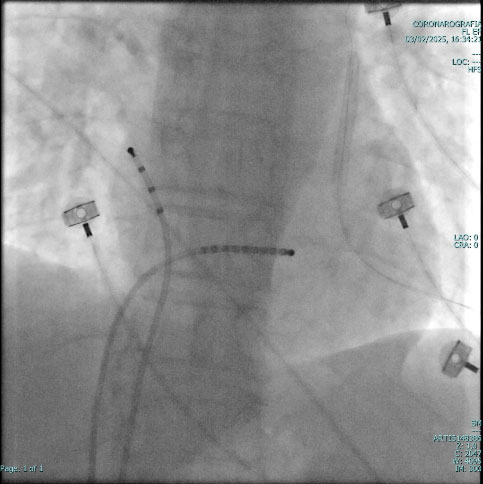

Oggi possiamo eseguire l'ablazione della fibrillazione atriale attraverso l'Elettroporazione.

L'innovazione tecnologica, unica nel suo genere, è di grande rilevanza: attualmente, infatti, tutte le procedure di ablazione cardiaca per il trattamento delle aritmie sono termiche, ivi comprese la radiofrequenza e la crioablazione. Nonostante l'evoluzione e i miglioramenti apportati nel tempo, queste forme di erogazione di energia vengono comunque ritenute rischiose, comportando possibili danni termici collaterali e indiscriminati ai tessuti vicini alla zona-bersaglio. Il nuovo sistema Farapulse PFA, invece, è caratterizzato da un'elevata selettività dei tessuti, produce piccolissime lesioni che durano solo pochi secondi e salvaguarda interamente le aree di tessuto cardiaco non coinvolto nella ablazione, con livelli di protezione e sicurezza inimmaginabili prima d'ora. Per questo, il sistema Farapulse per l'elettroporazione è ritenuta da molti clinici una fonte di energia affidabile e molto promettente per gli interventi di ablazione cardiaca, consentendo anche l'isolamento delle vene polmonari nel corso di trattamento della Fibrillazione Atriale.

Dotato del marchio CE dal 2021, il sistema è costituito da una guaina, un generatore e un catetere ed è disponibile in tutti i paesi Europei compresa, da poco, l'Italia. Va ricordato che l'ablazione cardiaca è una procedura minimamente invasiva, finalizzata a correggere alcune anomalie del Ritmo Cardiaco quali, per esempio, la Fibrillazione Atriale.

Nel corso della procedura, un catetere viene inserito nell'organismo attraverso l'inguine del paziente e guidato, fino a raggiungere l'interno del cuore. Nei sistemi di rimozione chirurgica tradizionale la punta del catetere predisposto per l'ablazione genera temperature estreme, molto calde o molto fredde, per eliminare il tessuto  malfunzionante e correlato ai battiti irregolari.

Il nuovo sistema Farapulse PFA si basa invece su campi elettrici pulsati, che non determinano effetti termici sui tessuti interessati ed agiscono esclusivamente sulle cellule bersaglio.

L'elettroporazione è un processo che utilizza impulsi elettrici per creare pori temporanei nelle membrane cellulari e rispetto alle tecniche tradizionali, come l'ablazione a radiofrequenza o con crioenergia, è una tecnica altamente selettiva che consente di danneggiare esclusivamente le cellule cardiache anomale, senza compromettere i tessuti sani circostanti. Questo approccio garantisce maggiore precisione e riduce il rischio di complicanze durante e dopo la procedura. Un altro punto di forza della tecnologia farapulse è la sua capacità di adattarsi alle caratteristiche anatomiche uniche di ogni paziente.